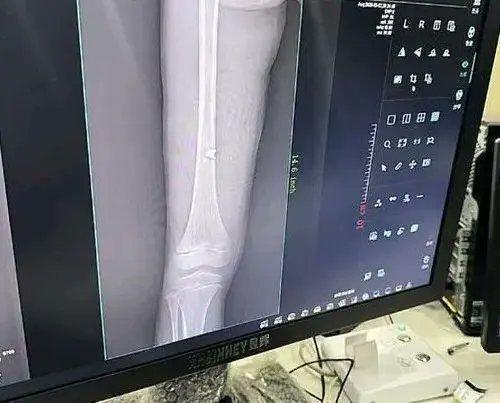

這名網民說,孩子以為是鞭炮要炸了,急忙往家裡跑,但幾秒後就爆炸,「爆炸威力比較大,鐵門被炸開7、8個大洞,房門口放著的拖把都被擊倒了。」這起事故發生後,女童的大腿也被彈片擊傷,根據x光檢查結果顯示,女童左腿腿骨內側,清晰可見嵌了一個彈片。